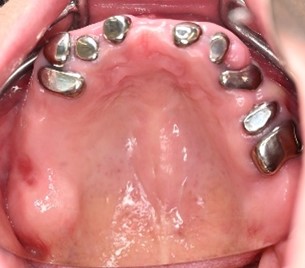

女性Tさん 50代(マグネット式入れ歯)

主訴

左上の犬歯が、グラグラして痛い

治療内容

他の歯も歯周病が進行していました。保存することができない歯が3本ありましたので、抜歯し、残った歯6本の歯周病治療をし、それらの歯を活用しマグネット式総入れ歯を入れました。

所感

マグネット式総入れ歯を活用し、もともとは反対交合でしたが、正常交合に改善することができました。

Before

赤丸は抜歯しました

After

【義歯を装着したところ】

【義歯を外したところ】

マグネット義歯

緑丸は組み込まれたマグネット